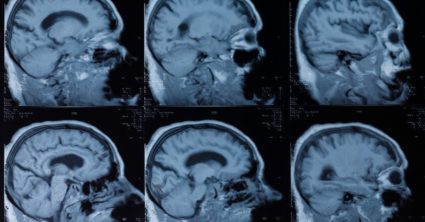

Padlo rozhodnutie vykonať ultrazvuk dolnej dutej žily nachádzajúcej sa blízko brucha, aby skontrolovali hladinu tekutín v cievach. Avšak pri tomto procese spozorovali, že v jeho žalúdku sa nachádza „tubulárna štruktúra, ktorá sa pohybovala krútením,“ napísali autori v správe zverejnenej v odbornom časopise The New England Journal of Medicine.